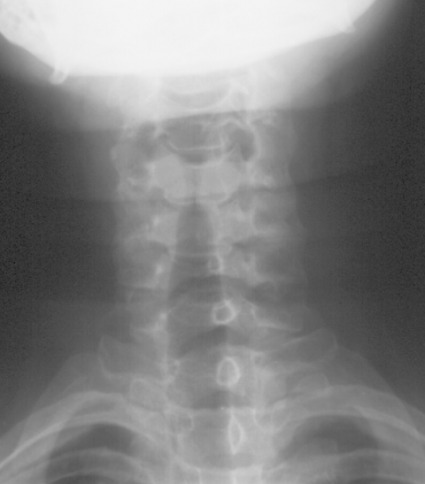

51 year old female presenting with neck pain and stiffness.  No history of trauma related by the patient. ​

1.  What are your key findings?

2.  What is your differential diagnosis?

3.  What is the appropriate follow up for this patient?